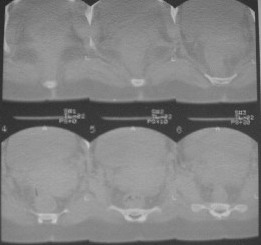

Из анамнеза: в ноябре 2002г. оступилась,упалана трап самолета (на верхней площадке, сразу при выходе из салона) на правый тазобедренный сустав, а затем - вниз на землю на ноги и ягодицы. Потеряла сознание от боли. Доставлена в больницу по месту жительства, лечилась консервативно с диагнозом кокцигодиния.На рентгенограмме от 27.11.02г. вывиха копчика не определяется (снимок идентичен представленной R-грамме от28.11.03г., кроме этого есть нормальная R-грамма копчика в боковой проекции).Через три недели стала ходить, но привести правую ногу в тазобедренном суставе не могла. Сейчас ходит отведя кнаружи правое бедро и голень, как ножку циркуля (фото 1). Неврологических нарушений нет. По просьбе врачаможет на 30-40 секунд поставить ноги вместе (фото 2). При этом испытывает сильную тянущую боль и ощущение "вывернутости" в правом тазобедренном суставе. Эти ощущения заставляют вновь отвести бедро. В положении лежа разогнуть бедро полностью не может из-за болей в ягодичной мышце (фото 3). Сгибание также ограничено из-за болей (фото 4). Отведение в положении лежа возможно в том же объеме, что и стоя (фото 5). Заподозрен старый разрыв правого крестцово-подвздошного сочленения.Выполнено R-исследование и КТ(в приложении). По-поводу деформации лонного сочленения выяснен гинекологический анамнез. Роды одни, нормальные в 22 года. Из роддома выписана на 8 сутки, нарушения походки не было, R-графия таза не проводилась. Вопросы на обсуждение: 1. Диагноз либо алгоритм дальнейшего обследования. 2. Лечебная тактика (в первую очередь возможность и целесообразность оперативного лечения).

Присоединияюсь к мнению д-ра Джолдаса Кульджанова - наиболее вероятно повреждение ацетабулярной губы - acetabular rim syndrome (ARS).

Отсутствие изменений сустава на КТ и обычных рентгенограммах, стойкие боли и ограничение подвижности в суставе - симптомы, характерные для повреждения ацетабулярной губы. ЯМР с контрастом или без должны прояснить картину.

Уважаемый Юрий Алексеевич, сделаны ли пациентке более дистальные срезы КТ с захватом области тазобедренного сустава? Учитывая давность травмы, могли присоединиться и дистрофические процессы в субхондральной кости головки и впадины. Изменения в капсуле будут хорошо видны на УЗИ, особенно в сравнении со здоровой стороной. Эффективность лечебно-диагностического введения гормональных препаратов, на мой взгляд, сомнительна ввиду давности патологического состояния. При такой стойкой и давней контрактуре без операции вряд ли можно обойтись. Под наркозом амплитуда на разгибание должна увеличиться, усилить эффект можно тено-миотомиями заинтересованных групп мышц, капсулотомией + в послеоперационном периоде хорошее консервативное противовоспатлительное лечение с укладками на разгибание.Что мешает приведению пока не ясно, во встретившихся в нашей работе аналогичных ситуациях причиной был формирующийся медиальный остеофит головки, выталкивающий её из впадины.